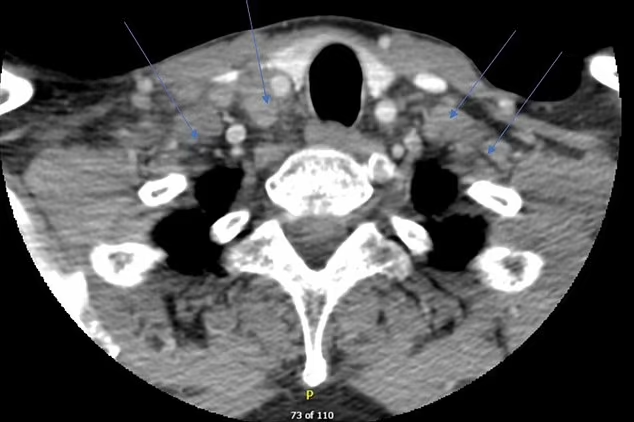

Soon after, he received two Pfizer Covid-19 shots. Months later, he developed headaches, fevers, drenching night sweats, and painful swelling in the glands on his neck. A scan showed enlarged lymph nodes. Doctors stopped his arthritis drugs and took a biopsy. The test pointed to tuberculosis, a bacterial infection that can stay quiet for years and then surge when the body’s defenses shift.